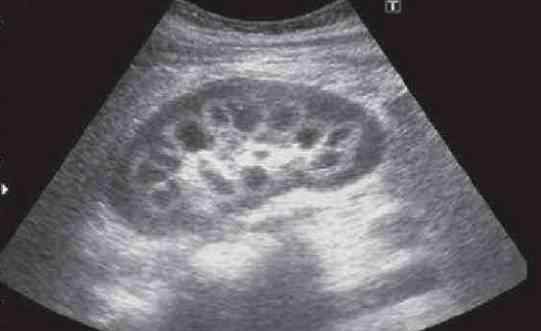

第二个孩子怀孕4个月,羊水化验后,肚子里的宝宝患了和大宝一样的病——肉碱缺乏症,在发育过程中不断从妈妈手里抢走肉碱。

“为了弄清孩子的死因,我们来到杭州女子医院找梅主任。她建议我们给婴儿做尸检和基因检查。”据王女士称,检查结果显示,该儿童患有严重的心肌病,是由原发性肉碱缺乏引起的,可导致心肌损伤和骨骼肌损伤。